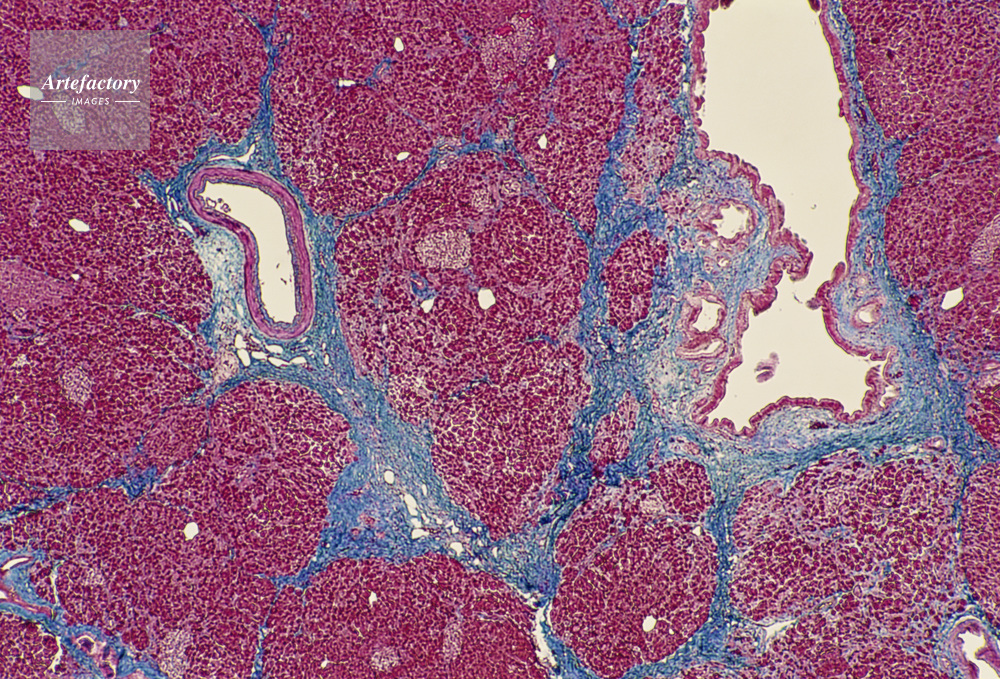

| キャプション | 脾臓,人間,20倍 | 制限事項 | ||

| ソース | ピクセル数 | 5559px × 3773px | ||